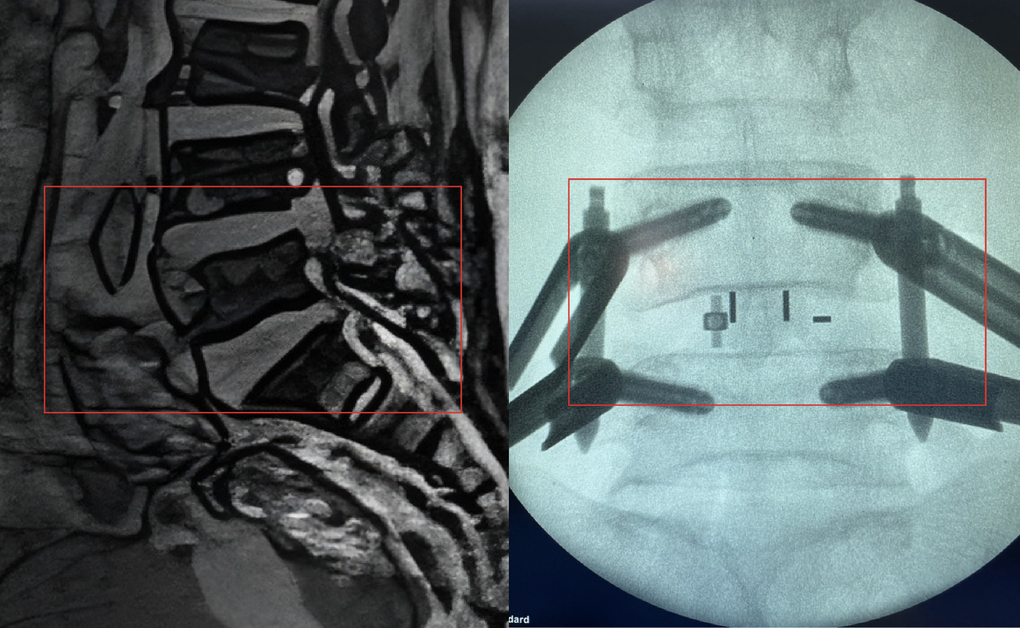

Based on clinical examination and MRI imaging diagnosis, Dr. Le Trong Nghia, Deputy Head of the Department of Neurosurgery - Spine, determined that Ms. B. had severe lumbar spinal stenosis causing compression of the L4-L5 nerve roots on both sides, due to spinal degeneration and ligamentum flavum, accompanied by L4-L5 disc herniation.

This condition has lasted for a long time, causing the patient's legs to almost lose feeling. If treatment is delayed, the patient may completely lose the ability to move the lower limbs.

Faced with that challenge, the surgical team considered and decided to choose the minimally invasive transforaminal lumbar vertebral body fixation (MIS-TLIF) method using a tube system, under C-arm guidance.

MIS-TLIF is a method of percutaneous screw placement and intervertebral fusion through the intervertebral foramen - the location where the nerve roots exit the spinal canal, effectively relieving nerve compression while minimizing invasion of healthy tissue.

Under the guidance of the modern C-arm system, X-ray images are provided in real time during surgery, doctors only need a small incision next to the spine in the L4-L5 region to access the damaged area with a microsurgical tube system. Doctors gently cut the articular processes and remove the herniated disc nucleus pulposus at the L4-L5 vertebrae to release the compressed spinal cord and nerve roots.

The team then placed a highly durable, compatible artificial biological disc to recreate the height of the spine, while also grafting the patient's own bone, and attaching 4 specialized screws used in minimally invasive surgery under the positioning of the C-arm machine integrated in the operating room.

The two vertebrae L4-L5 are firmly fixed, preventing spinal instability and helping the bone healing process better. In particular, the challenge in the surgery also comes from the issue of ensuring anesthesia safety and hemodynamic control in patients with high risk of surgical complications.

Image of L4-L5 vertebrae when the patient first entered the hospital (left) and after surgery (Photo: BVCC).